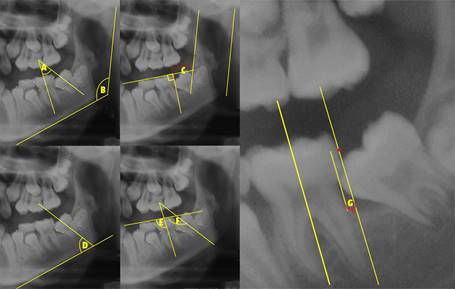

Las variables estudiadas en este trabajo fueron la medida del ángulo 2MM, como lo midió Evans1 y se le incorporaron puntos coronales para objetivar la medición descritos por Rubin et al.12(Fig. 1a). Se midió el ángulo goniaco (panorámico) trazando una línea al borde inferior del cuerpo mandibular y una tangente al borde posterior de la rama similar al trazado cefalométrico (Fig. 1b). Otra variable fue la distancia del primer molar (MM1) al borde anterior de la rama, para lo cual se trazó la línea del plano oclusal (PO) hasta la rama, se marcó una línea perpendicular al plano oclusal que pase por el punto más distal de la corona de MM1, a continuación se trazó una línea al borde posterior de la rama similar a la usada para medir el ángulo mandibular, después se marcó un punto en la parte más cóncava del borde anterior de la rama y se trazó una línea hasta el PO que pasara por este punto y que fuera paralela a la línea posterior de la rama. Finalmente la distancia es medida en milímetros sobre la línea del PO entre la línea vertical por distal del primer molar antes mencionadas y la línea vertical al borde anterior de la rama (Fig. 1c). Para medir el ángulo entre MM2 y plano mandibular se usó la línea del eje longitudinal descrito por Rubin et al.12 de MM2 y se extendió hasta la línea del plano mandibular, se midió el ángulo por anterior (fig. 1d). Para medir el ángulo de MM1 con PO, se usó el eje longitudinal del MM1 descrito por Rubin et al.12 y se extendió hasta el PO, el ángulo se midió por anterior (Fig. 1e). El ángulo MM2 y PO se obtuvo de la misma forma que el anterior usando el eje longitudinal del MM2 (Fig. 1f). La invasión de MM2 por distal del MM1, fue medida trazando una línea paralela al eje longitudinal de MM1 que pasara por el punto coronal más distal de MM1 y se midió en milímetros la cantidad de MM2 que se encontrara por delante de esta línea (Fig. 1g). Se observó la presencia o ausencia de terceros molares independiente de la etapa de desarrollo en la que se encontrara.